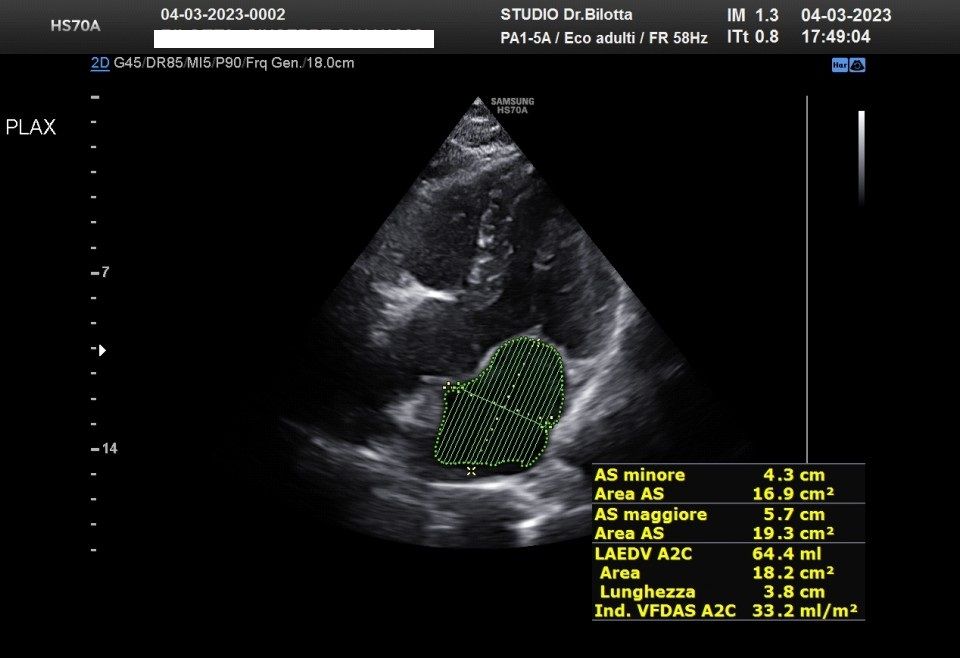

Diploma di maturità classica. Laurea in Medicina e Chirurgia con Lode a 26 anni. Specialista in Oncologia Generale Diagnostica e Preventiva con Lode a 31 anni. Specialista in Malattie Cardiovascolari a 36 anni. Medico generalista dal 1990 poi ospedaliero per trent'anni dal 1993 al 2022 nel corso dei quali ho refertato oltre 100 mila tracciati elettrocardiografici, effettuato oltre 30 mila consulenze specialistiche, praticato circa 10 mila esami ecocardiografici, condotto oltre 2 mila test ergometrici sia su cicloergometro che su treadmill, visionato circa 1500 esami Holter Ecg e ABP ( Ambulatory Blood Pressure ) occupandomi prevalentemente di prevenzione cardiovascolare, ipertensione arteriosa, cardiopatia ischemica, valvulopatie. Dal 2023 ho deciso di trasferire le mie competenze nella libera professione presso il mio studio privato che è stato allestito in linea alle moderne esigenze tecnologiche. Metodiche diagnostiche attualmente praticate: Elettrocardiografia a riposo, Ecocardiografia mono-bidimensionale, PW, CW, Colordoppler tridimensionale, GLS Strain Speckle tracking, Monitoraggio Holter Pressorio delle 24 ore, Monitoraggio Holter ECG 12 canali dinamico delle 24 ore.

Foto e video